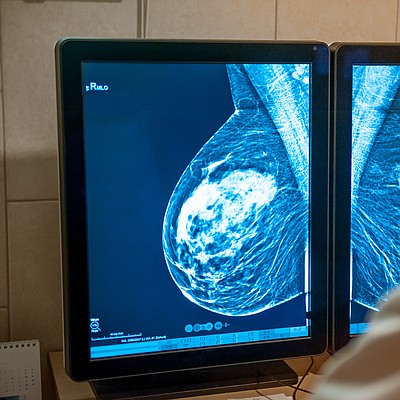

New ACR Breast Cancer Screening Guidelines call for earlier and more-intensive screening for high-risk women

New American College of Radiology® (ACR®) breast cancer screening guidelines now call for all women — particularly Black and Ashkenazi Jewish women — to have risk assessment by age 25 to determine if screening earlier than age 40 is needed. The ACR continues to recommend annual screening starting at age 40 for women of average risk, but earlier and more intensive screening for high-risk patients. The new ACR guidelines for high-risk women were published online May 3 in the Journal of the American College of Radiology (JACR).